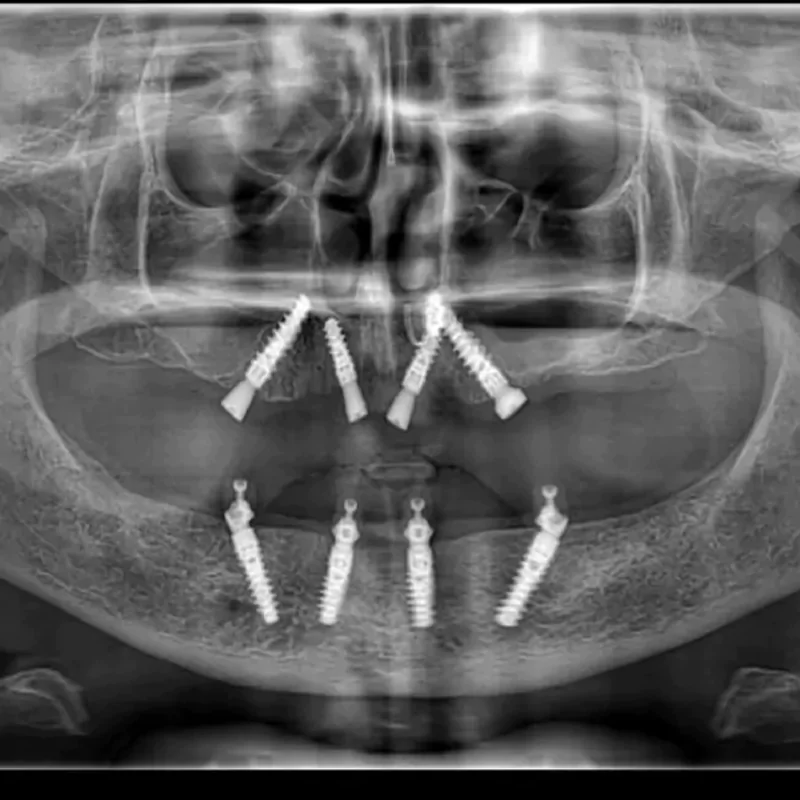

Since year 2000 we are Centre of excellence in implantology .We have done thousands of full mouth dental implant cases in last 25 years .We have a team approach where experienced implant surgeons , prosthodontists , maxillofacial surgeons , digital restorative dentists and lab technicians work together to deliver world class fixed teeth. We use multiple implant option from case to case. Some need All-on-4, some need All-on-6 or All-on-8 in selective cases.

All-on-4 Implants

It is a revolutionary concept in which only four implants support an entire arch of teeth. It is minimally invasive and cost-effective.

All-on-6 Implants

It is an advanced technique in which six implants support a full arch of teeth. It ensures superior stability, durability, and improved chewing function.